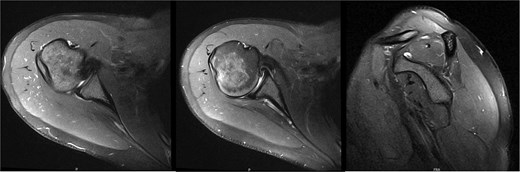

Six years following decompression, the patient presented for right shoulder pain and fatigue without new injury. Post-collegiately, she coached volleyball. MRI revealed a diffusely atrophic infraspinatus muscle belly (Fig. 3). On examination, she demonstrated persistent diminished infraspinatus, supraspinatus, and teres minor strength, pain in the Aber position, mild anterior apprehension, and a positive (+1) Sulcus sign. She proceeded with posterior capsular stretching and cuff strengthening.

MRI 6 years after decompression revealed a diffusely atrophic infraspinatus muscle belly.